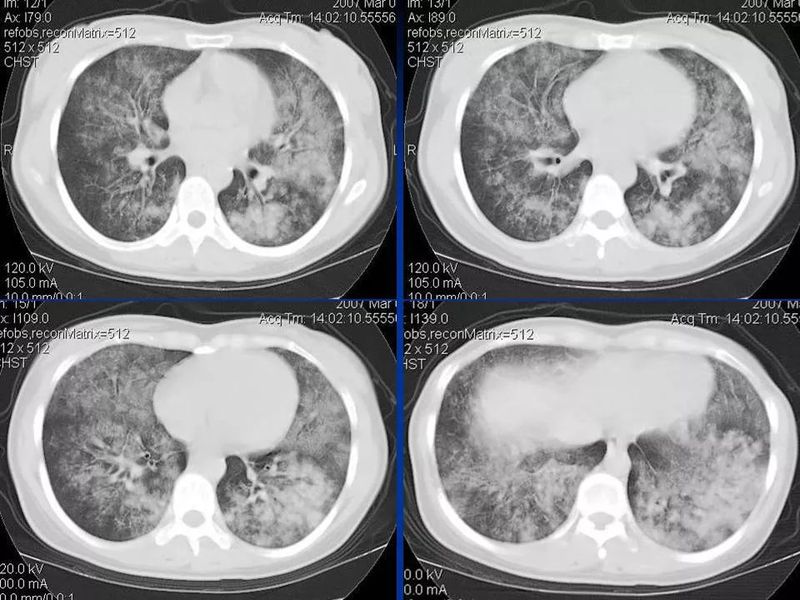

主任提醒:这个病很容易误诊为肺炎!